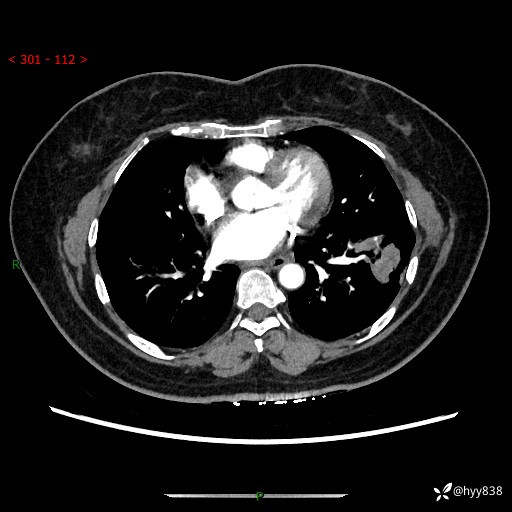

【现病史及既往史】:患者自诉2月前体检发现肺结节(左肺下叶约17mm,右肺上叶4mm),未予特殊处理,2024-10-12当地市第五医院门诊复查胸部CT提示右下肺结节(大小约3.3cm*3.9cm),患者无咳嗽、咳痰,无畏寒、发热、盗汗,无咯血,无胸闷、胸痛、呼吸困难,无恶心、呕吐,无腹痛、腹胀、腹泻等不适,现为求进一步诊治,门诊以“孤立性肺结节”收住我科。 患者本次起病来精神、食欲、睡眠尚可,大小便正常,体力、体重无明显变化。

【检查】:胸部CT增强检查